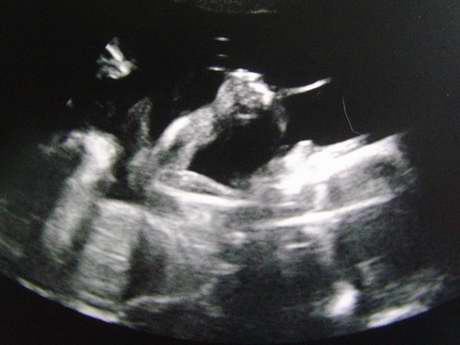

[第二次4D超音波-31w3d]

今天是照第二次4D超音波的日子,

不過因為老大要值班,所以只有我一個人去照....

沒想到小菜包卻意外的賞臉,今天把臉轉過來了....

我家小菜包可愛的臉~.

*偷偷睜開眼睛,護士講的時候我還沒發現哩,右眼有偷偷瞇開。

*才誇獎他今天好乖,沒想到馬上手就來了,還把手指頭塞進嘴裡。

手指頭還滿修長的說...XD。

*快結束時,小菜包開始打嗝,側面可以看到微微的抖動好幾下。

今天我的寶貝小菜包真的很乖哩....^^